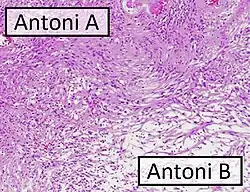

| Micrograph of a schwannoma showing both a cellular Antoni A area (top) and a loose paucicellular Antoni B area (bottom). HE stain. | |